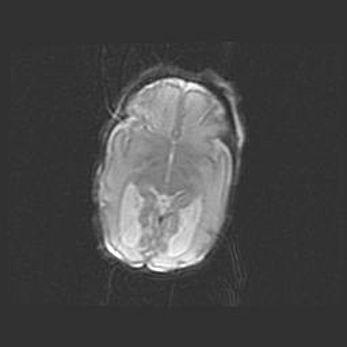

Сообщающаяся гидроцефалия. Кистозная энцефаломаляция головного мозга.

Возраст: 3 месяца 4 дня

Вес: 3100 г

Пол: женский

Окружность головы: 34 см

Срок гестации: 31 неделя

Кистозная энцефаломаляция головного мозга - одна из форм поражения головного мозга в детском возрасте. Характеризуется возникновением множественных и распространённых кист в коре, белом веществе и подкорковых образованиях головного мозга у плодов, новорождённых и детей раннего возраста. Развитие кистозной энцефаломаляции связано с внутриутробной асфиксией и гипотонией, родовой травмой, тромбозом синусов, пороками развития сосудов, инфекциями, сепсисом и другими причинами. Наиболее значимые инфекционные агенты: вирусы простого герпеса, цитомегалии, краснухи, токсоплазмы, энтеробактерии, золотистый стафилококк и другие.